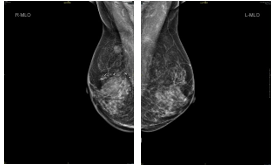

•  2018-10-16 钼靶:右乳内份肿块,BI-RADS 0

•  2018-10-23 彩超:右乳富血供肿块(BI-RADS 4C类,考虑MT,建议穿刺)

2疗程治疗后评估:PR

右乳癌治疗后较前好转,右乳头后方导管扩张同前,BI-RADS:6。 右腋下小淋巴结同前。左乳未见明显异常,BI-RADS:1